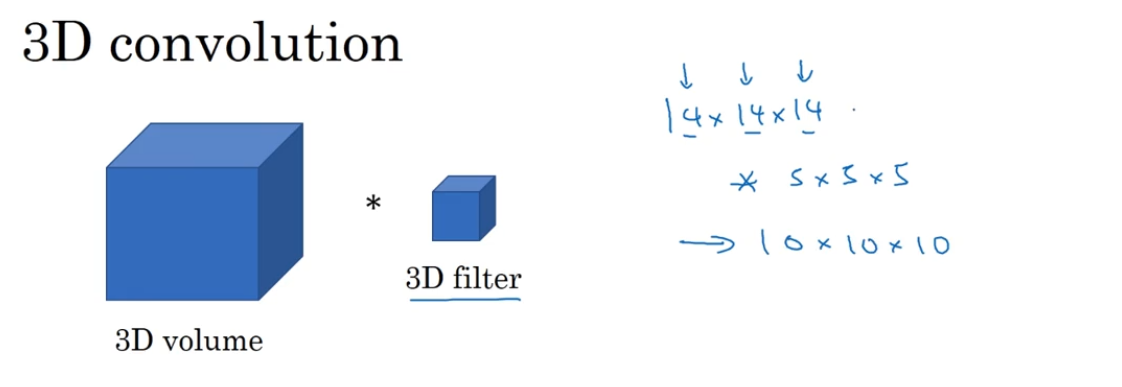

假设输入图像是14×14,卷积核大小为5×5。或许图像可能是3通道,所以卷积核为5×5×3,如果你使用了多重过滤,比如16,最终你得到的是10×10×16。

如果你想要在3D扫描或CT扫描中应用卷积网络进行特征识别,你也可以从3D卷积的第一行开始,为了简单起见,如果你有一个3D对象,比如说是14×14×14

技术上来说你也可以再×1(通道数),前面的14×14×14仅仅只是一个3D模块,如果你使用16个过滤器,那么输出就是10×10×10×16